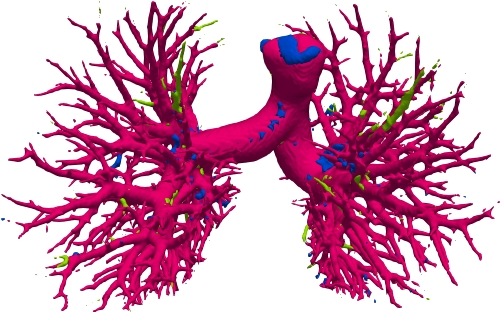

We qualitatively analyze our method on four challenging lung organ datasets. In Fig. 5, SFCN [19] suffers from severe false positives and some false negatives, especially for the big green areas of airway leakages. WNet [22] is mainly influenced by false negatives on the main trachea. For the Fibrosis dataset at the third row, it also encounters the false negative problem in the terminal bronchioles moderately. FANN [10] bears the slight discontinuity issue of false negative in the terminal bronchioles of BAS dataset, and the severe discontinuity and airway leakage problems on the more challenging Fibrosis benchmark. Instead, due to the above two novel modules, our method can solve the defects of false negative, discontinuity, and leakages faced by past advanced methods. Besides, the results on PARSE22 artery dataset in supplementary Fig. 6 also proves this.

Comparison on PARSE22 dataset. This dataset is more challenging due to more dense small bronchioles shown in supplementary Fig. 6. However, our method still reaches the best weighted average multi-level dice of 84.96% in Table 2 compared against some advanced methods via the official evaluation. As you can see, the remarkable gain comes from the “branch artery”, which maintains the consistency with above airway segmentation.